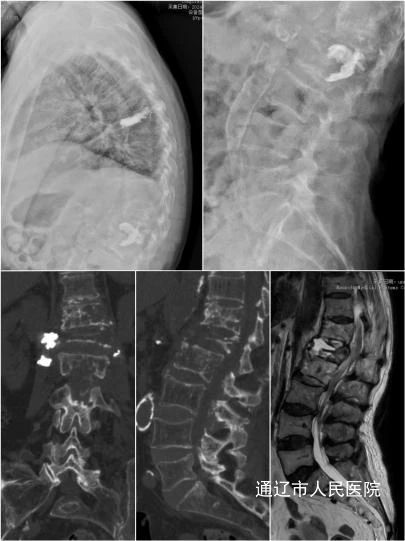

近日,我院脊柱外科应用Ponte截骨联合卫星棒技术成功为一位脊柱结核后凸畸形患者实施重建手术,标志着我院在界内脊柱矫形手术领域再获突破。

患者杨某某,74岁,女性,因胸腰背部疼痛10月余入住我院,该患者曾辗转多家医院,检查提示脊柱结核(T12-L2),为求进一步诊治遂前往我院就诊。针对患者恶病质体质病情特点,术前团队内部积极讨论手术方式。结合多学科会诊评估结果,与患者及家属充分沟通并征得同意后,房芳主任医师、胡宝阳主治医师在麻醉科医护人员的通力协作下,成功为患者实施胸椎后路切开椎板减压、Ponte截骨、骨水泥椎弓根钉内固定术(T10-L4),手术过程顺利,术后患者恢复良好,得到患者及家属一致好评。